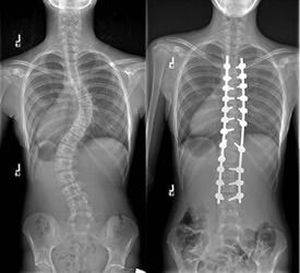

Scoliosis is the abnormal lateral or sideward curve to the spine. It is common in children, and it may be caused by congenital malformation, poliomyelitis, limbs of unequal length, among other factors. Early treatment involving surgery, casts, exercises, and braces may prevent progression of the curvature.